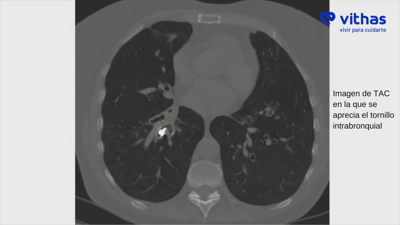

Sácanlle un parafuso que tiña nos bronquios dende había sete meses

A muller, de 70 anos, aspirara sen decatarse a peza de titanio despois dunha cirurxía dental